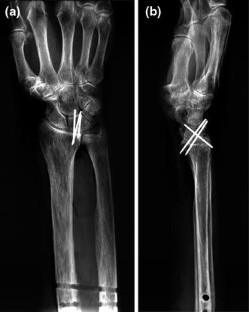

Radiolunate arthrodesis was simulated in three fresh human cadaver wrists by means of Kirschner wires. Individual motion of the scaphoid, triquetrum and capitate relative to the radius was measured for extension/flexion and radial–ulnar deviation before and after arthrodesis. Photostereogrammetric measurement was carried out and the helical axis concept of motion was employed.

Fig. 1